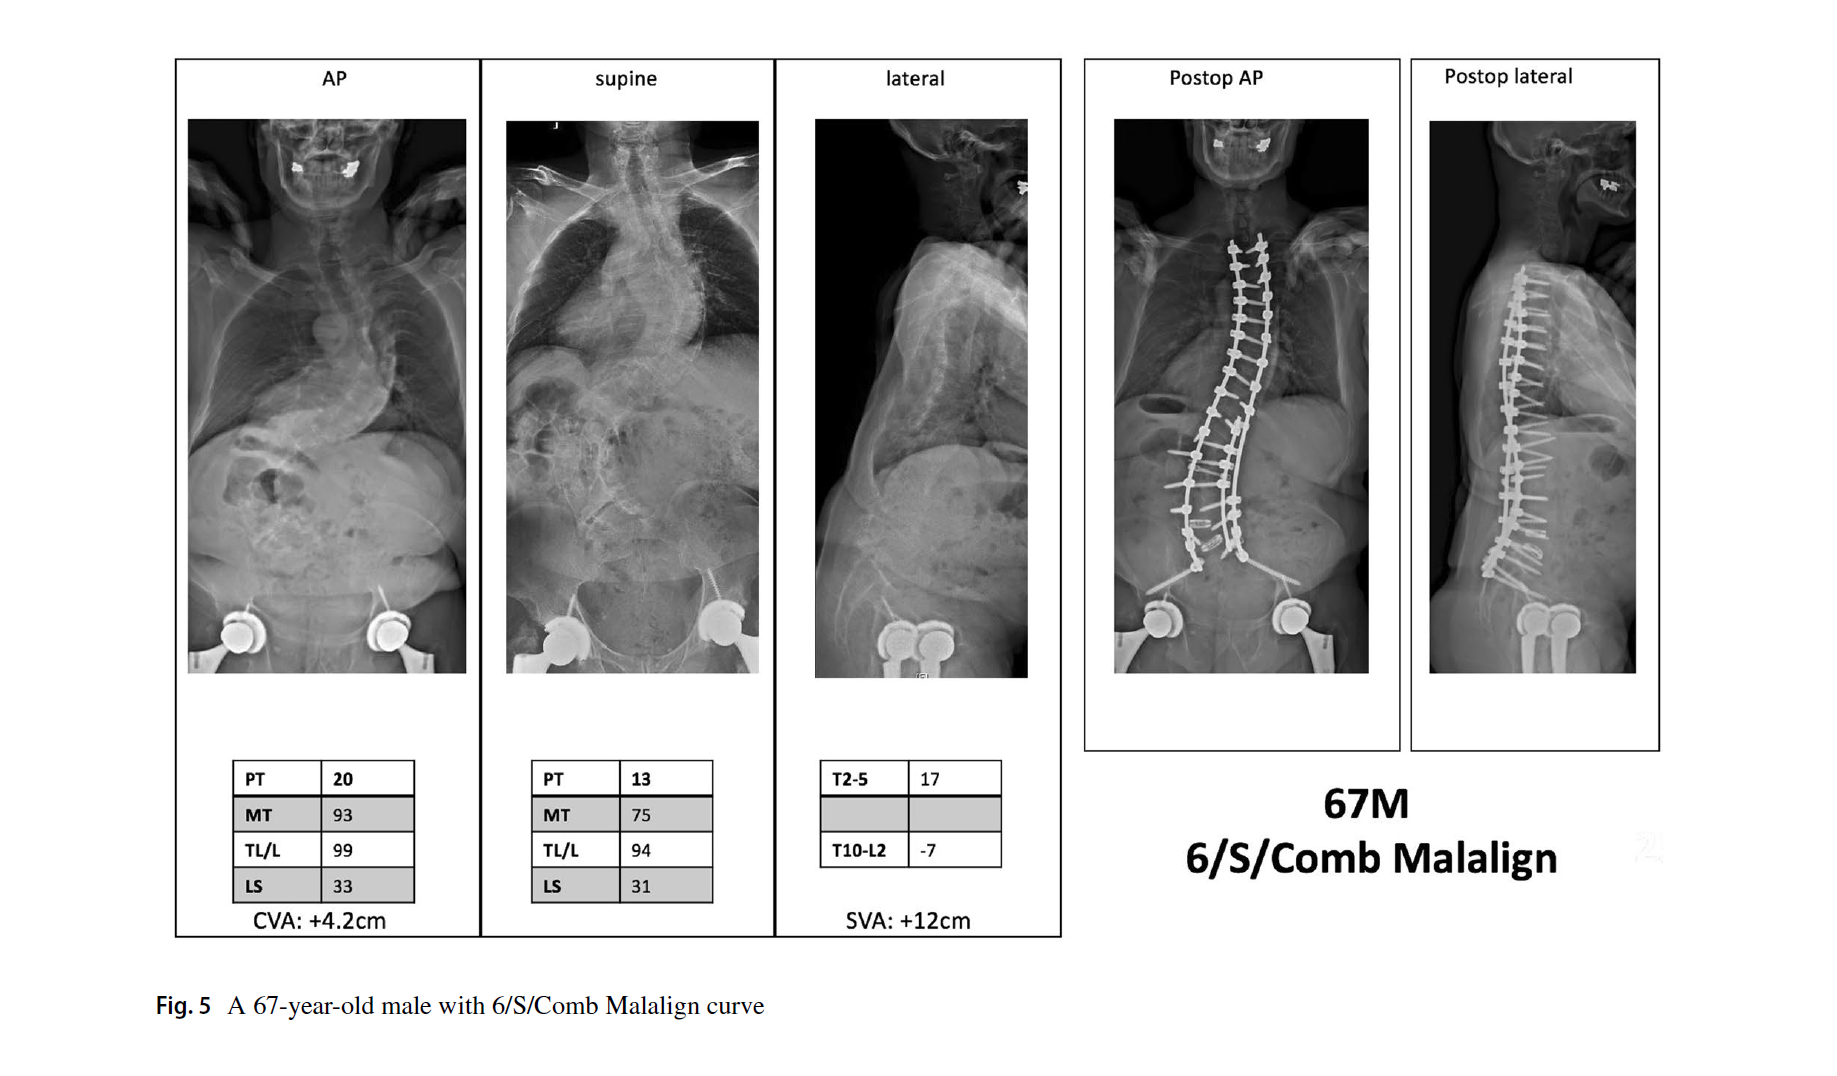

2. 腰骶椎修正,是本分型的特别和关键之处。定义为仰卧位片L4上终板到S1上终板的Cobb角。大于20度为结构弯(S),需要融合腰骶段。小于20度为非结构弯(NS),不需要融合腰骶段。

3. 脊柱平衡修正包括了冠状位、矢状位和冠矢合并的平衡状态。标准与SRS基本一致,冠状位失衡CVA≥40mm,矢状位失衡SVA≥40mm。排列组合,共有Aligned、Sag Malalign、Cor Malalign、or Comb Malalign 4种类型。如果脊柱失衡,需要按SRS标准矫正。

文中的病例片子很漂亮,看图知意,很容易让读者理解这个分型。